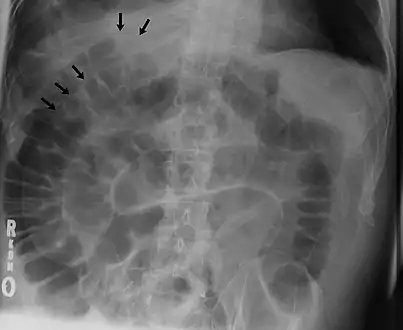

Signs that can be seen on projectional radiography are shown below:

The double wall sign marks the presence of air on both sides of the intestine.[19] However, a false double wall sign can result from two loops of bowel being in contact with one another.[20] The sign is named after Leo George Rigler.[21] It is not the same as Rigler's triad.

The football sign is when the abdomen appears as a large oval radiolucency reminiscent of an American football on a supine projectional radiograph.[22] The football sign is most frequently seen in infants with spontaneous or iatrogenic gastric perforation causing pneumoperitoneum. It is also seen in bowel obstruction with secondary perforation, as in Hirschprung disease, midgut volvulus, meconium ileus and intestinal atresia. Iatrogenic causes like endoscopic perforation may also give football sign.

The Cupola sign is seen when air is accumulated under the central tendon of the diaphragm.[23]